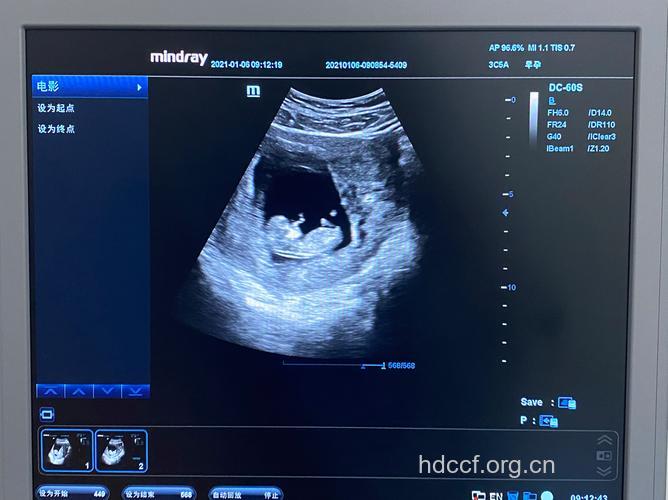

此时胎儿在积极地锻炼喝水的能力。专家认为胎儿喝水训练主要是出于一种生存的本能,即为了训练自己的生活本领。胎儿通过对口腔吸吮能力的锻炼,以便为出生后使用口唇吃奶做好准备。

第四月末:子宫底达脐与耻骨联合上缘之间,子宫底大约在耻骨联合以上10厘米左右。